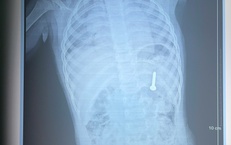

Cứu người bị áp xe ổ bụng hiếm gặp do mắc xương cá

Tin nóng y tế - 09/10/2025 20:05SKĐS - Chiều 9/10, Bệnh viện Lê Văn Việt (TPHCM) cho hay, các bác sĩ khoa Ngoại Tổng hợp vừa phẫu thuật thành công một ca áp xe ổ bụng do dị vật xương cá có thể nguy hiểm đến tính mạng nếu chậm trễ xử trí.